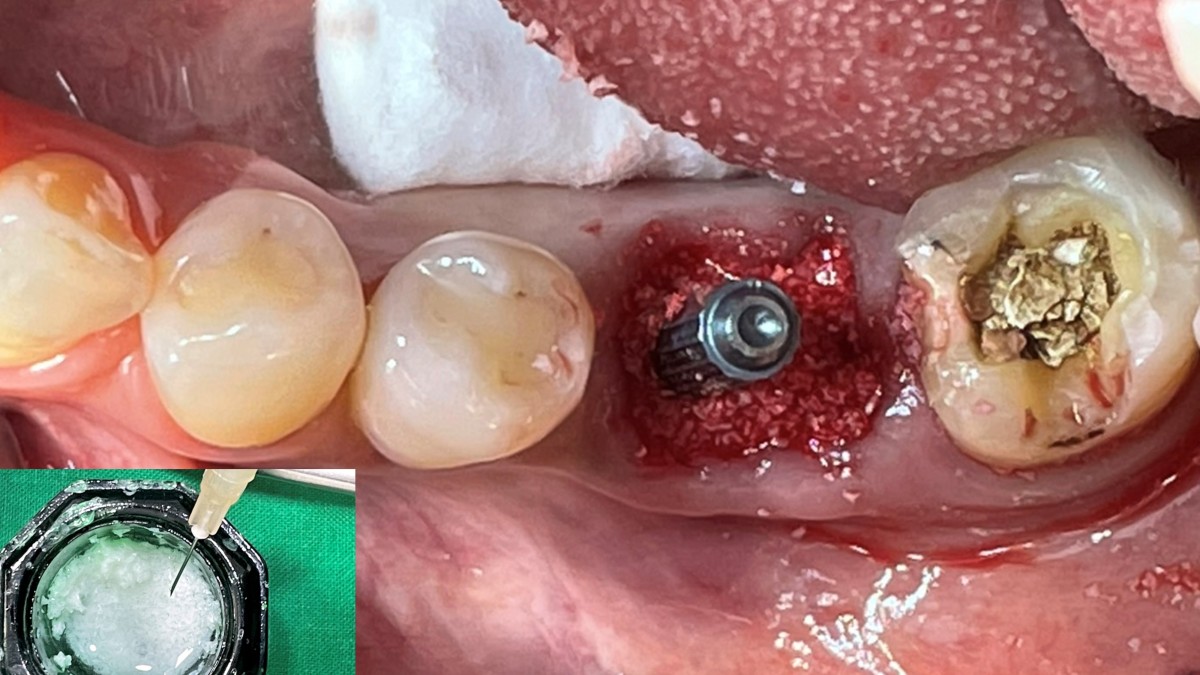

Immediate placement of an implant (Arum Dnetistry NB1, 5*8.5)

Extraction and immediate placement of an implant.

▲Arum Dentistry NB1 fixture (5*8.5mm)